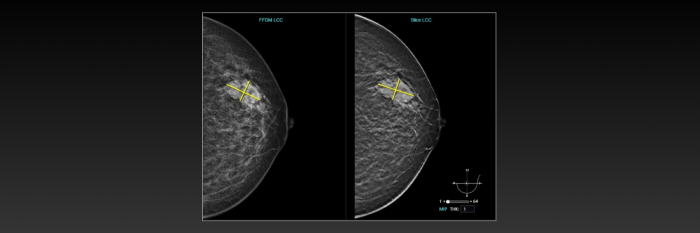

基于最新BI-RADS分类,联影智能DBT乳腺智能分析系统能够自动评估乳腺腺体密度类型,精准检出肿块、钙化、结构扭曲和不对称四大常见病灶,并提供病灶的详细信息,还能够自动生成BI-RADS分类和报告文本,既降低漏诊率,也显著减轻医生的工作负担,使其更专注于诊断本身。